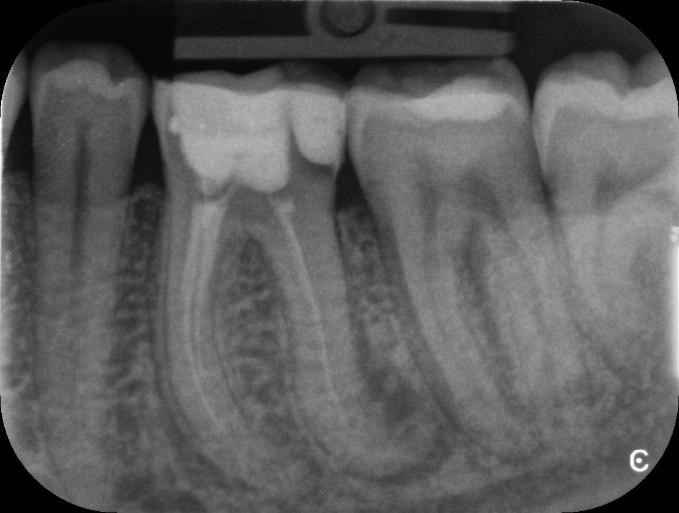

Lower Molar and premolar Primary root canal treatment